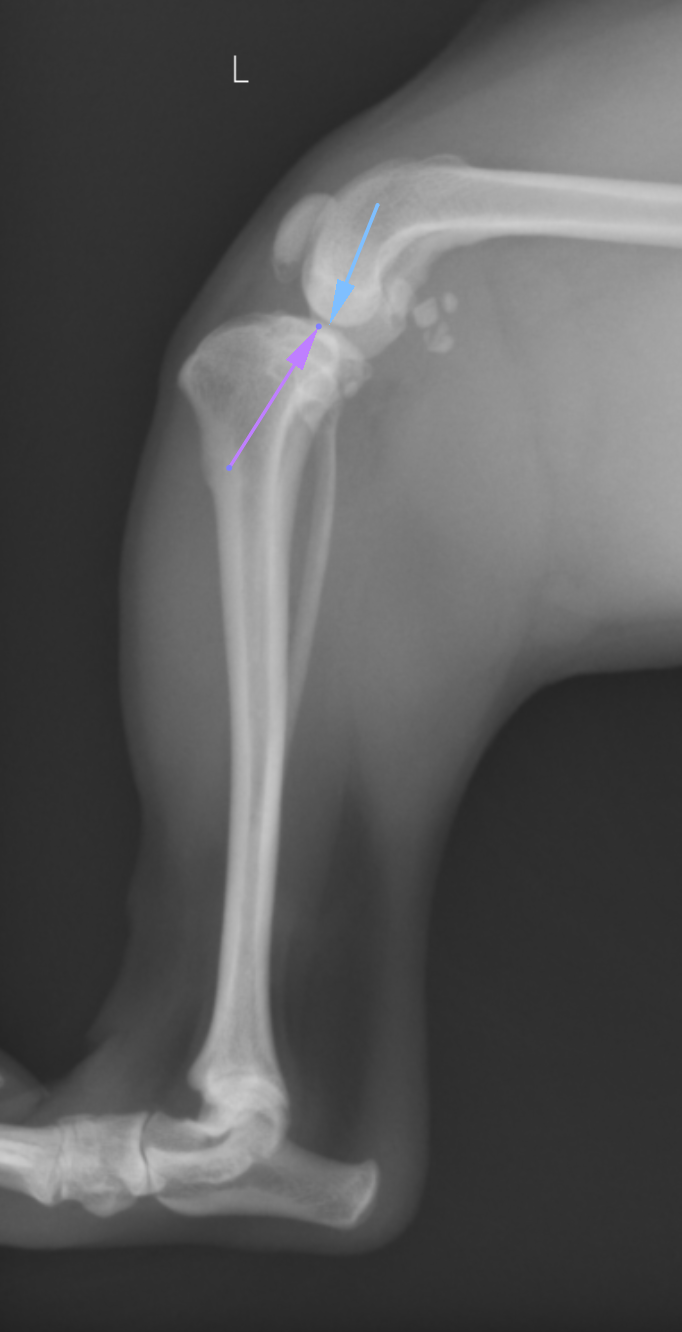

前十字靭帯は膝にある重要な靭帯で、犬における最も一般的な損傷の1つと言われており、膝関節の変形性関節疾患の主な原因です。靭帯の損傷には、重度な不安定性を伴う完全断裂の場合と、軽度の不安定性を伴う不完全(部分)断裂の場合があります。いずれにしても無処置の場合には数週間で変形性関節疾患の症状を呈し、数力月で重度な変化を示します。前十字靭帯断裂を伴う犬の30~40%において、対側の靭帯も2年以内に断裂することが知られ ています。 膝蓋骨内方脱臼と前十字靭帯断裂の併発はトイ種の大に比較的多く認められます。これらの症例において膝蓋骨内方脱臼は初期条件で、前十字靭帯断裂は膝蓋骨が脱臼し、膝関節と脛骨が不安定になり、前十字靭帯が伸びたために生じた可能性が高いと言われています。 前十字靭帯の治療法には大きく分けて内科治療か外科治療に分かれます。内科治療にはバンテージや薬による鎮痛、サポーターなどが挙げられますが、その治療効果は限定的です。特に体重が大きくなるほど内科的治療は困難となります。 外科治療には以前から実施されてきた関節外制動術(Flo法など)や機能的安定化術(TPLOなど)がありますが、現在ではTPLOという術式が最も成績が良く、合併症も少ないということで多く実施されています。その成績は元の運動を100としたときに、ほぼ100まで戻すことができるのがTPLO、Flo法が80%程度、TTAという手術が80-90%程度と報告されています。

TPLOは脛骨高平部という部分を水平にする術式ですが、その優れた点として、骨を円形に切断することで、関節の回転中心を変化させない、骨に伝わる重心を変化させないというものが挙げられます。前十字靭帯が切れてしまうとTPAという脛骨高平部の角度があるが故に脛骨が前方に進んでいこうとします。これを脛骨前方運動=CrTTと言います。斜めの椅子に腰掛けると椅子が後ろにすすむのをイメージするとわかりやすいかと思います。TPAを水平にすることで、前十字靭帯が断裂していてもCrTTが生まれない足にしてしまうというのがTPLOになります。